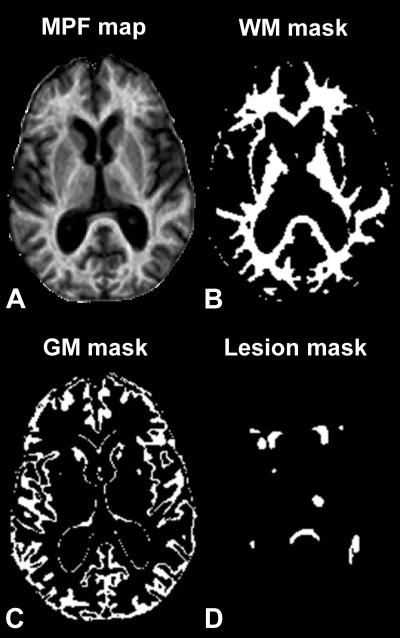

To learn more about associations between MS and demyelination in both white and gray matter, Dr. Yarnykh and colleagues used a refined MRI technique that provides information on the content of biological macromolecules – molecules present in tissues and composed of a large number of atoms, such as proteins, lipids and carbohydrates. The new method, known as macromolecular proton fraction (MPF) mapping, has been hampered in the past because of the length of time required for data collection, but improvements now allow much faster generation of whole-brain maps that reflect the macromolecular content in tissues.

"The method utilizes a standard MRI scanner and doesn't require any special hardware—only some software modifications," Dr. Yarnykh said. "MPF mapping allows quantitative assessment of microscopic demyelination in brain tissues that look normal on clinical images, and is the only existing method able to evaluate the myelin content in gray matter."

The researchers looked at 30 MS patients, including 18 with relapsing-remitting MS (RRMS), the most common type of MS initially diagnosed, and 12 with the more advanced type of disease known as secondary progressive MS (SPMS). Fourteen healthy control participants were also included in the study. Each participant underwent MRI on a 3-Tesla imager, and the researchers reconstructed 3-D whole-brain MPF maps to look at normal-appearing white matter, gray matter and MS lesions. The researchers further compared the results of their imaging technique with clinical tests characterizing neurological dysfunction in MS patients.

The results showed that MPF was significantly lower in both white and gray matter in RRMS patients compared with healthy controls, and was also significantly reduced in both normal-appearing brain tissues and lesions of SPMS patients compared to RRMS patients with the largest relative decrease in gray matter. MPF in brain tissues of MS patients significantly correlated with clinical disability and the strongest associations were found for gray matter.